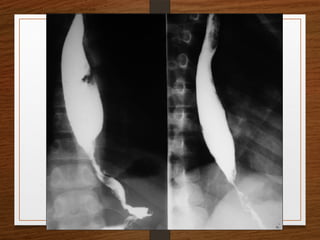

Contrast Films

• Barium Swallow

• Barium Meal

Barium Studies

Barium studies can demonstrate GI abnormalities in three ways

1. Mucosal relief views of the collapsed or partially collapsed

lumen obtained with a small volume of barium.

• particularly useful for showing abnormalities involving the

submucosa, such as esophageal varices.

2. Single-contrast views of the filled lumen obtained with a

large volume of low-density barium

• These views enable visualization of contour abnormalities,

strictures, and large polypoid defects.

3. Double-contrast views obtained after the mucosal surface

has been coated with a thin layer of high-density barium

and the lumen has been distended with gas

• These views enable visualization of subtle mucosal lesions, such as

the early changes of inflammatory bowel disease and early

neoplastic lesions

• Barium suspensions for single-contrast studies

should be of moderate density (50%-100% w/v)

when not diluted.

• For the double-contrast examination, we use high-

density 250% w/v barium